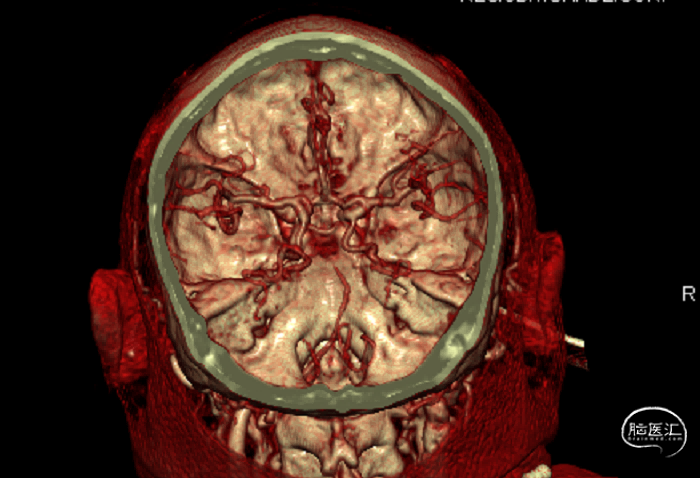

综合术前辅助检查,(Core+pen)/Core=3.58;Pen>15ml;Core<70ml(图3);发病时间小于24小时,存在取栓指征,但是当地医院手术经验告诉我们左侧椎动脉慢性闭塞,且开通异常困难,常规手术方案很难成行,术前制定合理且可行的手术方案至关重要。方案1:仍采用左侧椎动脉+基底动脉取栓的正向开通方案,可能会继续浪费大量时间,甚至最后以失败告终。方案2:采用右侧椎动脉入路,由于右侧椎动脉V4段发育不良,当地医院已尝试过超选,证实无法通过V4段至基底动脉建立取栓通路。方案3:既往有文献报道开颅椎动脉直视下穿刺取栓,虽然方案可行,但我院无类似手术经验,贸然尝试风险难以把控。方案4:回顾当地医院取栓影像资料,发现双侧颈内动脉后交通呈胚胎型,是否可能通过后交通跨循环逆向超选至基底动脉取栓。患者平卧DSA床,全麻插管成功后,用碘伏常规消毒手术区皮肤,铺无菌巾单。取双侧股动脉为穿刺点,于14时00分seldinger法穿刺成功后分别置入8F穿刺鞘和5F 短鞘。行全脑血管造影显示左侧椎动脉起始部闭塞,颈升动脉通过肌支代偿V2及以远的椎动脉血流,右侧椎动脉V4段发育不良,单纯供应右侧PICA,双侧后交通动脉胚胎型。(图9,图10)首先我们仍尝试传统入路进行超选左侧椎动脉,发现左侧椎动脉开口闭塞,斑块质地坚硬,微导丝微导管无法通过。短暂尝试无果后,迅速改为右侧椎动脉入路,发现将微导丝塑型成“J”型或成袢,均无法到达右侧椎动脉V4段,遂果断决定采用跨循环取栓方案。将5F VERT造影导管超选至左侧锁骨下动脉,进行正向血流监测。6F 90cm长鞘(cook)及5F 125cm Navien导管在泥鳅导丝带领下超选进入右侧颈内动脉岩骨段。随后将Rebar18微导管在Synchro2微导丝带领下超选至大脑中动脉,并将Navien带领至右侧颈内动脉交通段。微导丝微导管回撤至颈内动脉,路图下Synchro2微导丝带领Rebar18逐步通过右侧后交通动脉,再在透视下经右侧大脑后动脉P1段盲超选至基底动脉下段。(图11-13)手推造影确认Rebar18微导管已突破血栓段,并在基底动脉真腔内。(图14)经Rebar18释放一枚solitaire FR支架(4mm×20mm)覆盖血栓段。SWIM技术负压下抽拉支架1次,抽拉过程中时刻注意系统张力,逐步回撤支架同时适度回撤Navien释放张力,以保证Navien贴近后交通开口而不向后交通动脉内继续深入。撤出支架后,Navien原位保持负压约30秒。(图15)造影复查见基底动脉及其分支再通,支架取出少量血栓(图18)。于14时45分达到远端血流mTICI3级,10分钟后复查造影显示血管通畅,于14时55分末次造影见远端血流维持mTICI3级。(图16,17)术中Dynamic CT未见明显术区出血(图19)。遂缝合穿刺点,结束手术。手术顺利,术中病人情况稳定。术末血压115/58mmHg,脉搏70次/分,呼吸12次/分,氧饱和度100%。术毕送重症监护室。图9. 双侧椎动脉造影:左侧椎动脉起始部闭塞,左侧颈升动脉肌支和右侧椎动脉通过脊髓支代偿V2及以远的椎动脉血流;右侧椎动脉V4段发育不良,单纯供应右侧PICA